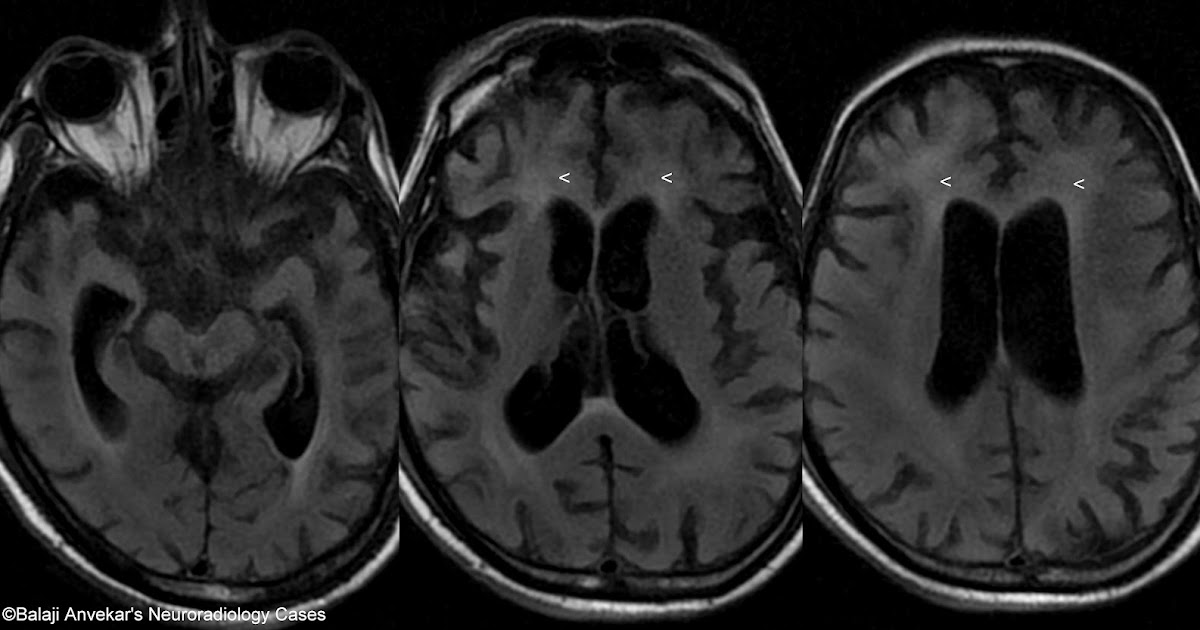

From www.neuroradiologycases.com

Dr Balaji Anvekar FRCR HIV Encephalitis Vs PML Hiv Brain Atrophy Radiology Direct consequence of the hiv virus. We present a pictorial review of a range of central nervous system (cns) conditions in patients with human immunodeficiency virus (hiv). Hiv/aids affects the cns by one of four mechanisms: Magnetic resonance imaging (mri) can improve the outlook for people with hiv through early diagnosis and prompt treatment. Mass lesions, meningoencephalitis, demyelination, atrophy, and. Hiv Brain Atrophy Radiology.

Brain atrophy in HIV/AIDS, MRI scans Stock Image C058/2245 Hiv Brain Atrophy Radiology Magnetic resonance imaging (mri) can improve the outlook for people with hiv through early diagnosis and prompt treatment. Hiv/aids affects the cns by one of four mechanisms: Direct consequence of the hiv virus. Magnetic resonance imaging (mri) can improve the outlook for people with hiv through early diagnosis and prompt treatment. We present a pictorial review of a range of. Hiv Brain Atrophy Radiology.